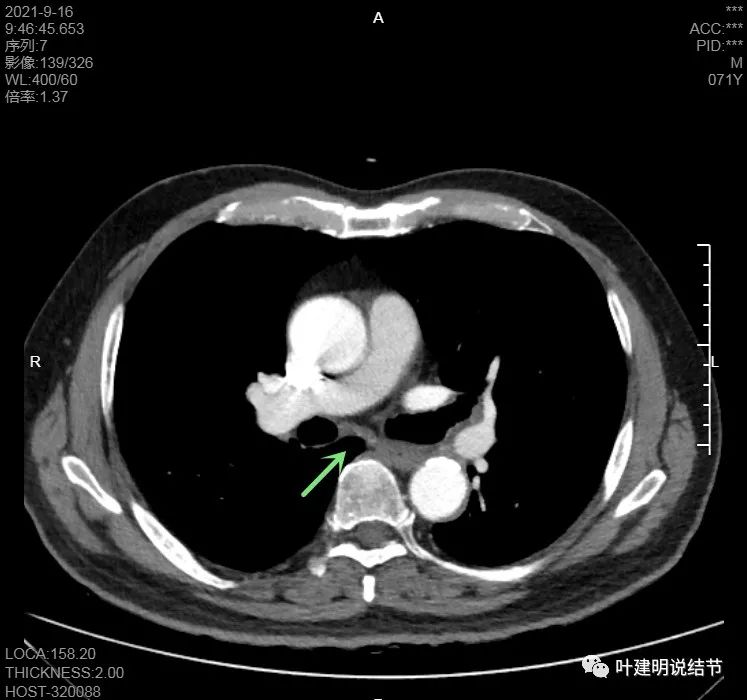

隆突下未见明显肿大淋巴结

左肺门区淋巴结肿大

肺门区淋巴结挤压附近肺血管,但似乎示见肿瘤侵犯破坏血管壁